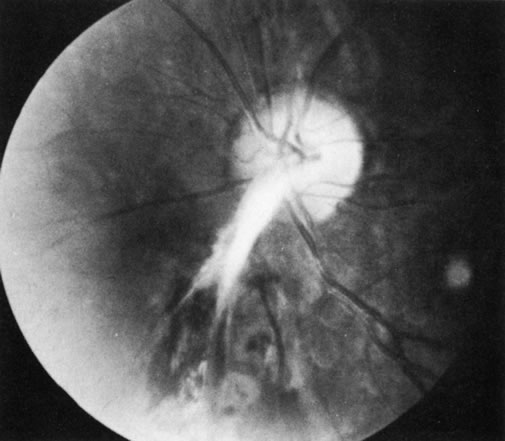

Behçet's disease is a chronic inflammatory disease with widespread clinical manifestations. It affects adults of both sexes, especially in Mediterranean countries and Japan. Classically it consists of a triad of recurrent lesions: iritis, oral ulcers, and genital ulcers (Fig. 6).34 Other common features are vasculitis, skin lesions, optic papillitis (Fig. 7), arthritis, meningomyelitis, and inflammatory bowel disease. Loss of vision is one of its most frequent and serious manifestations. In Japan, the disease is said to be responsible for one-third of all cases of uveitis. Ocular disease occurs in 75% of affected patients, usually in the form of hypopyon, uveitis, occlusive retinal vasculitis, and optic nerve lesions. The cause of Behçet's disease is unknown, but viral, immunologic, and hereditary factors have been suspected.

Fig. 6. Hypopyon iritis in Behçet's disease. (Courtesy of Dr. K. Yamaguchi.)

Fig. 7. Optic papillitis in Behçet's disease. (Courtesy of Dr. G. Mintsioulis.)